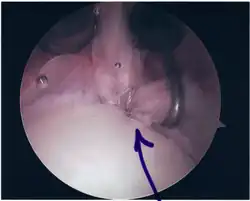

SLAP Tear

Repair of SLAP Tear

Arthroscopic SLAP Lesion (type 2) repair

Following inspection and determination of the extent of injury, the basic labrum repair is as follows.

• The glenoid and labrum are roughened to increase contact surface area and promote re-growth.

• Locations for the bone anchors are selected based on number and severity of tear. A severe tear involving both SLAP and Bankart lesions may require seven anchors. Simple tears may only require one.

• The glenoid is drilled for the anchor implantation.

• Anchors are inserted in the glenoid.

• The suture component of the implant is tied through the labrum and knotted such that the labrum is in tight contact with the glenoid surface.